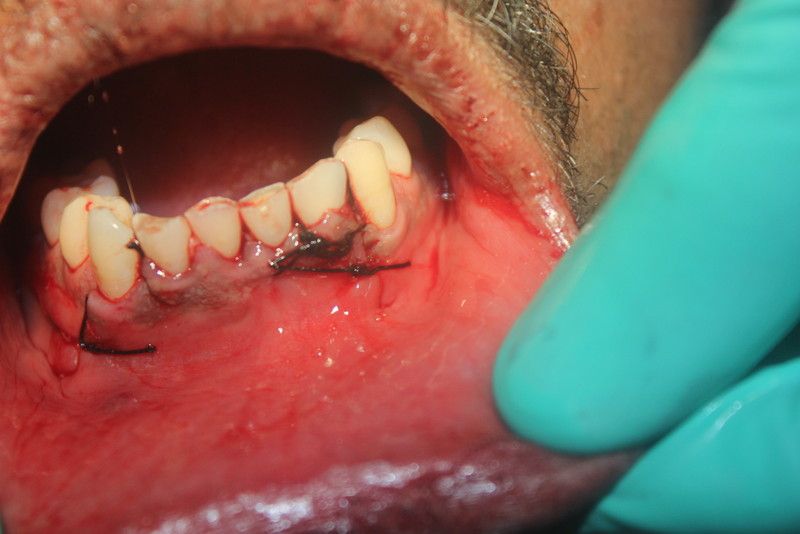

Dental Implants and Autogenous Bone Grafting